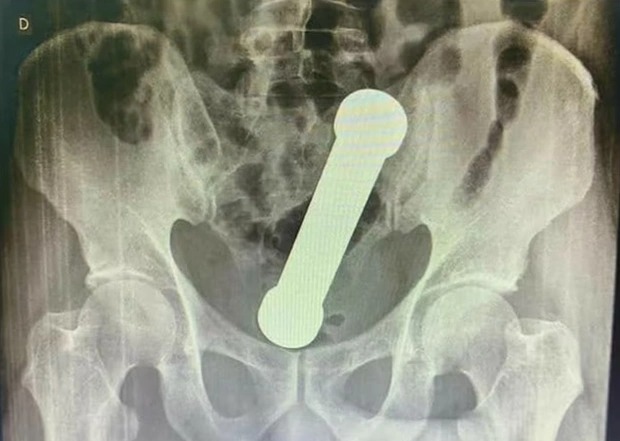

16/04/2022 16:06Nam bệnh nhân kêu đau trực tràng, bác sĩ hết hồn khi xem phim chụp X-quang

Câu chuyện bắt đầutrong một bệnh viện tại thành phố Manaus, bang Amazonas, Brazil khi một bệnh nhân 54 tuổi nhập viện trong tình trạng đau bụng, buồn nôn và không thể đi vệ sinh.

Người này cho biết hai hôm trước bắt đầu thấy đau bụng nhưng phải đến khi cảm thấy mọi chuyện không ổn và vượt quá sức chịu đựng anh này mới tìm đến bệnh viện. Khi kiểm tra sơ bộ các bác sĩ vẫn chưa thể đưa ra kết luận về nguyên nhân gây bệnh, vì vậy họ quyết định chụp X-quang cho bệnh nhân.

Đến khi cầm tấm phim chụp trên tay, các bác sĩ đã không khỏi hốt hoảng khi phát hiện một dị vật hình trụ dài 20cm trong cơ thể người bệnh giống như một quả tạ. Lúc này nạn nhân mới cho biết trước đó anh đã cố gắng tự mình lấy "vật thể" ra khỏi cơ thể nhưng không thành công, tuy nhiên người này không cho biết nguyên nhân trước đó có sự xuất hiện của món đồ này.

Các bác sĩ sau đó đã trấn an người bệnh và tiến hành phẫu thuật với ý định ban đầu là dùng nhíp để gắp vật thể ra tuy nhiên vì là một khối tạ kim loại nên việc này bất khả thi. Phương án cuối cùng được lựa chọn là các bác sĩ tự tay lôi "nó" ra ngoài, bệnh nhân sau đó cũng nhanh chóng hồi phục sức khỏe và xuất viện sau 3 ngày.

Viết trên Tạp chí phẫu thuật quốc tế, các bác sĩ cho biết, thường những trường hợp như này mọi người thường ít nói về nội tình sự việc bởi hầu hết đều liên quan đến vấn đề tình dục.

Các chuyên gia cho biết: “Dị vật xuất hiện trong trực tràng và bị giữ lại là một trường hợp hiếm khi xảy ra ở khoa cấp cứu trước đây, nhưng ngày càng xảy ra nhiều hơn trong những năm gần đây”.

Họ cũng cho biết dị vật nằm trong trực tràng chủ yếu là các dị vật có tính chất như những món đồ chơi tình dục, tiếp theo là các dị vật bằng thủy tinh. Những ca như vậy không chỉ đến từ cánh mày râu mà cũng xuất hiện khá nhiều ở các chị em phụ nữ.

Trong trường hợp các dị vật bị kẹt trong trực tràng cần phải có sự can thiệp y khoa của bác sĩ. Việc tự ý lấy dị vật ra rất có thể sẽ làm cho tình trạng trầm trọng thêm và nguy hiểm đến sức khỏe.